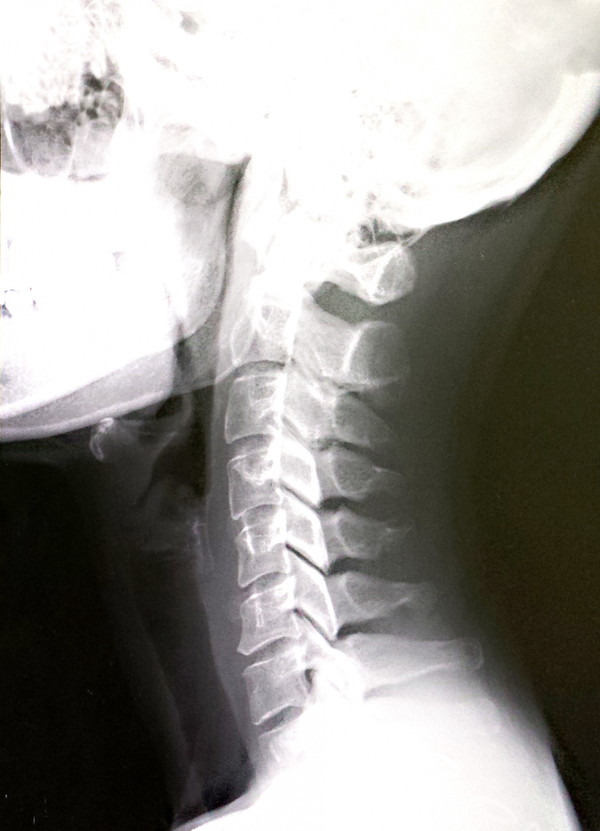

自律神経は、呼吸や体温、血圧、消化吸収など、生きていくために必要な機能のすべてを自動的に調整しており、自律神経は交感神経副交感神経に分けられます。

頚椎がズレて脊髄に障害が起こると、脳、脊髄、自律神経の機能が障害されます。

脳や脊髄の損傷や圧迫が起こると下半身麻痺などが起こる為どなたでも自覚しやすい一方、それに対して自律神経の圧迫は自覚しにくい不調として現れるため対処が遅れて慢性化しやすいことが多いです。